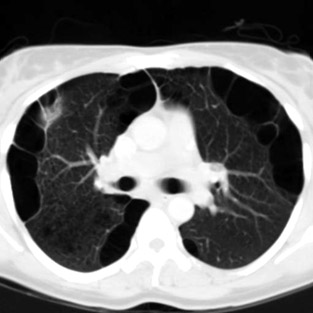

O Pneumotórax é causado por uma lesão na parede do pulmão (também chamada de pleura visceral) em que o ar sai do pulmão (como em uma bexiga furada), porém não retorna para dentro deste, acumulando-se na cavidade. Este acúmulo pode gerar um aumento importante da pressão na cavidade, atrapalhando ou impedindo o pulmão de encher-se de ar, impossibilitando a respiração por aquele pulmão. Também, o aumento da pressão pode ser tão importante a gerar um desvio de todo o mediastino (coração, grandes vasos) para o outro lado, atrapalhando toda função circulatória, podendo causar grave hipotensão e até morte. Este caso é chamado de pneumotórax hipertensivo.

O pneumotórax é classificado quanto a sua causa: espontâneo ou não. Causas de pneumotórax não espontâneo são traumas torácicos, como acidentes veiculares, tiros ou facadas; iatrogênicos, em que um tratamento médico o causa, como na passagem de um catéter em veias profundas ou barotraumas, causados por aumentos das pressões intrapulmonares, por exemplo, em pacientes em ventilação mecânica

O pneumotórax espontâneo é dividido em primário ou secundário. Os primários são causados por rompimentos de blebs, que são áreas de fraqueza da parede pulmonar onde acredita-se que sejam causadas pelo crescimento rápido do órgão. Estas se localizam geralmente no ápice dos pulmões e são mais frequentes em pessoas do biotipo longilíneo (magras e altas). Geralmente ocorre em pacientes jovens e tem frequência pouco maior em tabagistas.

Os secundários são gerados por rompimento de bolhas pulmonares, também áreas de fraqueza das paredes, causadas por doenças pulmonares subjacentes. A mais frequente, responsável por mais de 90% dos casos é o DPOC (doença pulmonar obstrutiva crônica) causada pelo tabagismo. Outras causas são esclerodermia, tuberculose, fibrose cística, entre outras.